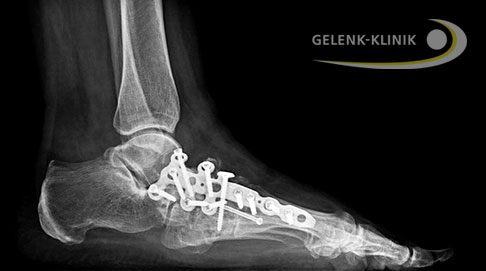

Röntgenbilder eines fortgeschrittenen Müller-Weiss-Syndroms vor OP (oben) und nach Versteifungsoperation (Arthrodese, unten). Der Kahnbeinknochen ist stark geschädigt und hat eine ausgeprägte Fehlstellung des Fußes verursacht. Der Operateur hat die Stellung des Fußes durch die Versteifung der Gelenke zwischen Sprungbein und Kahnbein (Talonavikulargelenk) sowie der Gelenke zwischen Kahnbein und Keilbeinen mittels Schrauben und Spangen korrigiert. Der Knochendefekt wurde mit Knochenspänen aus dem Beckenkamm des Patienten ausgeglichen (autologer Knochentransfer). © Gelenk-Klinik

Röntgenbild der Triple-Arthrodese aller drei Abschnitte des unteren Sprunggelenks (USG). © Gelenk-Klinik.de